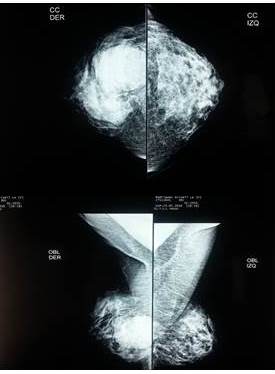

Paciente femenina de 30 años de edad presenta una masa tumoral en mama derecha de crecimiento rápido de 3 meses de evolución, no tiene antecedentes de enfermedad de neurofibromatosis en el grupo familiar ni ella lo presenta. Al examen físico se encuentra una masa tumoral de 16 cm. En diámetro mayor, firme no adherida a la piel ubicada en unión de cuadrantes externos (Figura 1). La paciente venía con una mamografía (Figura 2) y una ecografía mamaria (Figura 3)